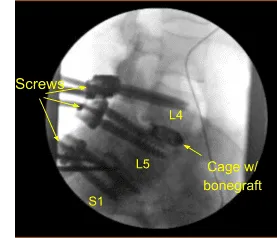

Demineralized bone matrix allograft was placed into the interspace and then titanium expandable interbody device was placed under fluoroscopic guidance after sterilely draping the C-arm unit. AP and lateral imaging showed correct positioning and then the cage was expanded to the proper fit and the subsequent x-ray showed good positioning both in the midline and anteroposterior.

Next, a new CT scan was obtained, which showed correct positioning of the new pedicle screws and interbody spacer. Bilateral transverse processes of L4, L5, and lateral ala were decorticated for arthrodesis. Pre-cut, pre-contoured rods reflected and placed across the tulips from L4 to S1 and secured with locking caps and finally tightened with the torque and anti-torque device.